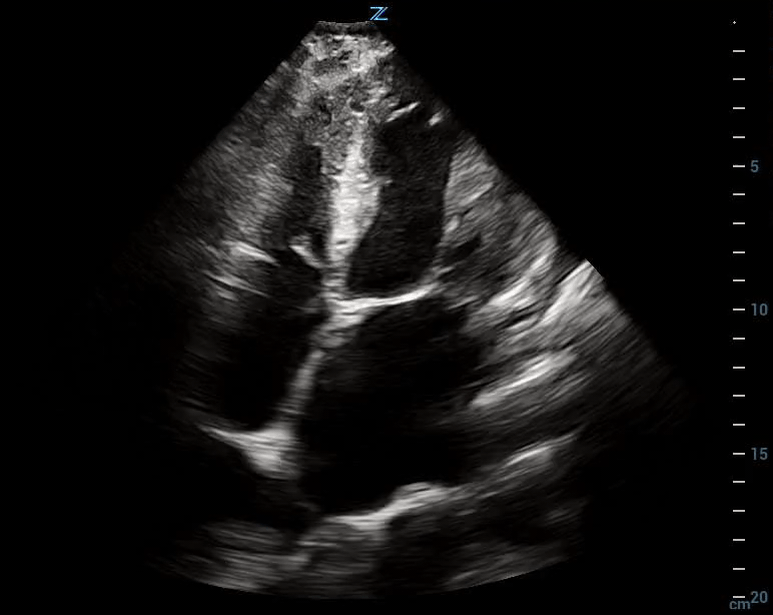

Mild Left Ventricular Dysfunction

Case 1:

Mild LV dysfunction a small pericardial effusion as well as a left sided pleural effusion

Case 2:

Mild LV dysfunction